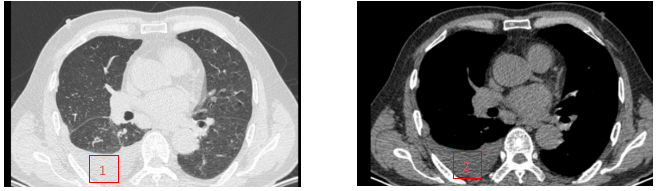

术 前

术后2月

1、胸腔积液(肺窗);2、胸腔积液(纵隔窗);3、1、胸腔积液(肺窗);2、胸腔积液(纵隔窗);3、胸腔积液消失(肺窗);4、胸腔积液消失(纵隔窗)。